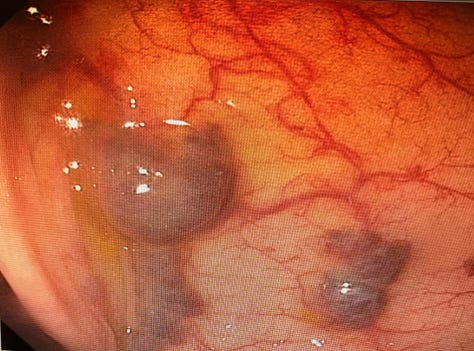

Case 3: A Rare Finding - Blue Rubber Bleb Nevus Syndrome

Case Summary: A series of images showcased the characteristic lesions of Blue Rubber Bleb Nevus Syndrome, a rare vascular disorder.

Key Teaching Points:

•Recognizing the Syndrome: This case served as a great reminder of the endoscopic appearance of this rare syndrome, which is characterized by multiple blue or purple vascular nevi throughout the GI tract and skin.

•Clinical Significance: These lesions can be a source of chronic gastrointestinal bleeding and anemia.